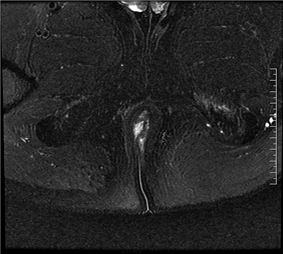

(MRI影像示意图,展示肛瘘常见表现)

在MRI图像中:

◆ 活动期肛瘘MR常表现为T2WI高信号,增强明显强化;

◆ 寻找内口以T1WI增强序列最佳,其次为T2WI抑脂序列,内口影像表现为括约肌内点状T2WI高信号,明显强化或括约肌受牵拉,括约肌间隙消失;

◆ 直径<1CM为瘘管,瘘道的管径最宽处直径>1CM的局限膨隆为脓肿;

◆ 肛瘘愈合期或慢性期,T2WI常表现为低信号,强化减弱或无强化。